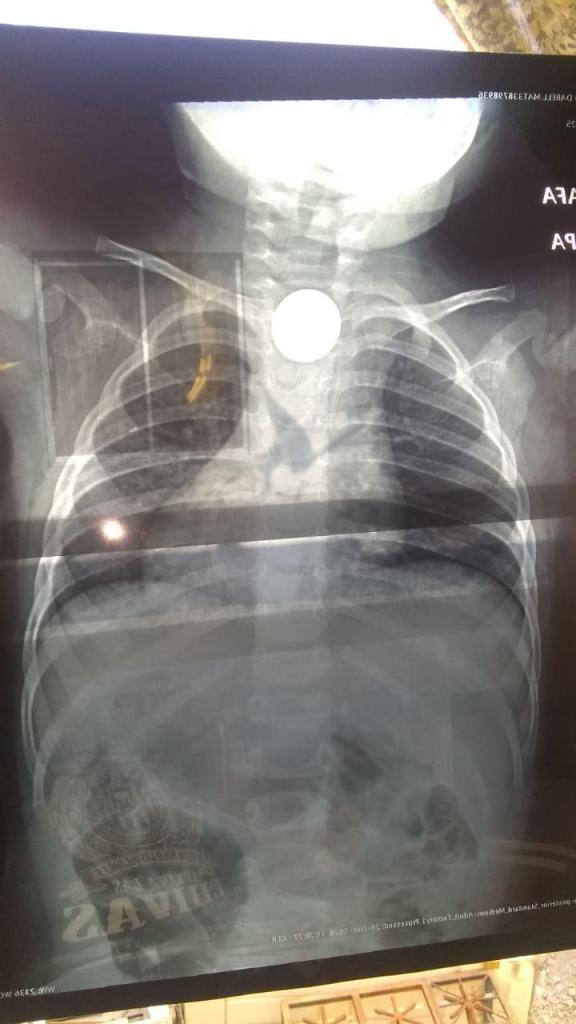

De manera accidental se tragó una moneda y es urgente retirarla ya que su vida corre peligro.